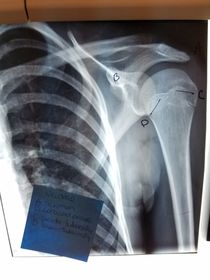

Which projections/positions are these? (top->bottom) TOP: Scapular Y-View _________________________ BOTTOM: AP External Rotation (greater tubercle in profile)